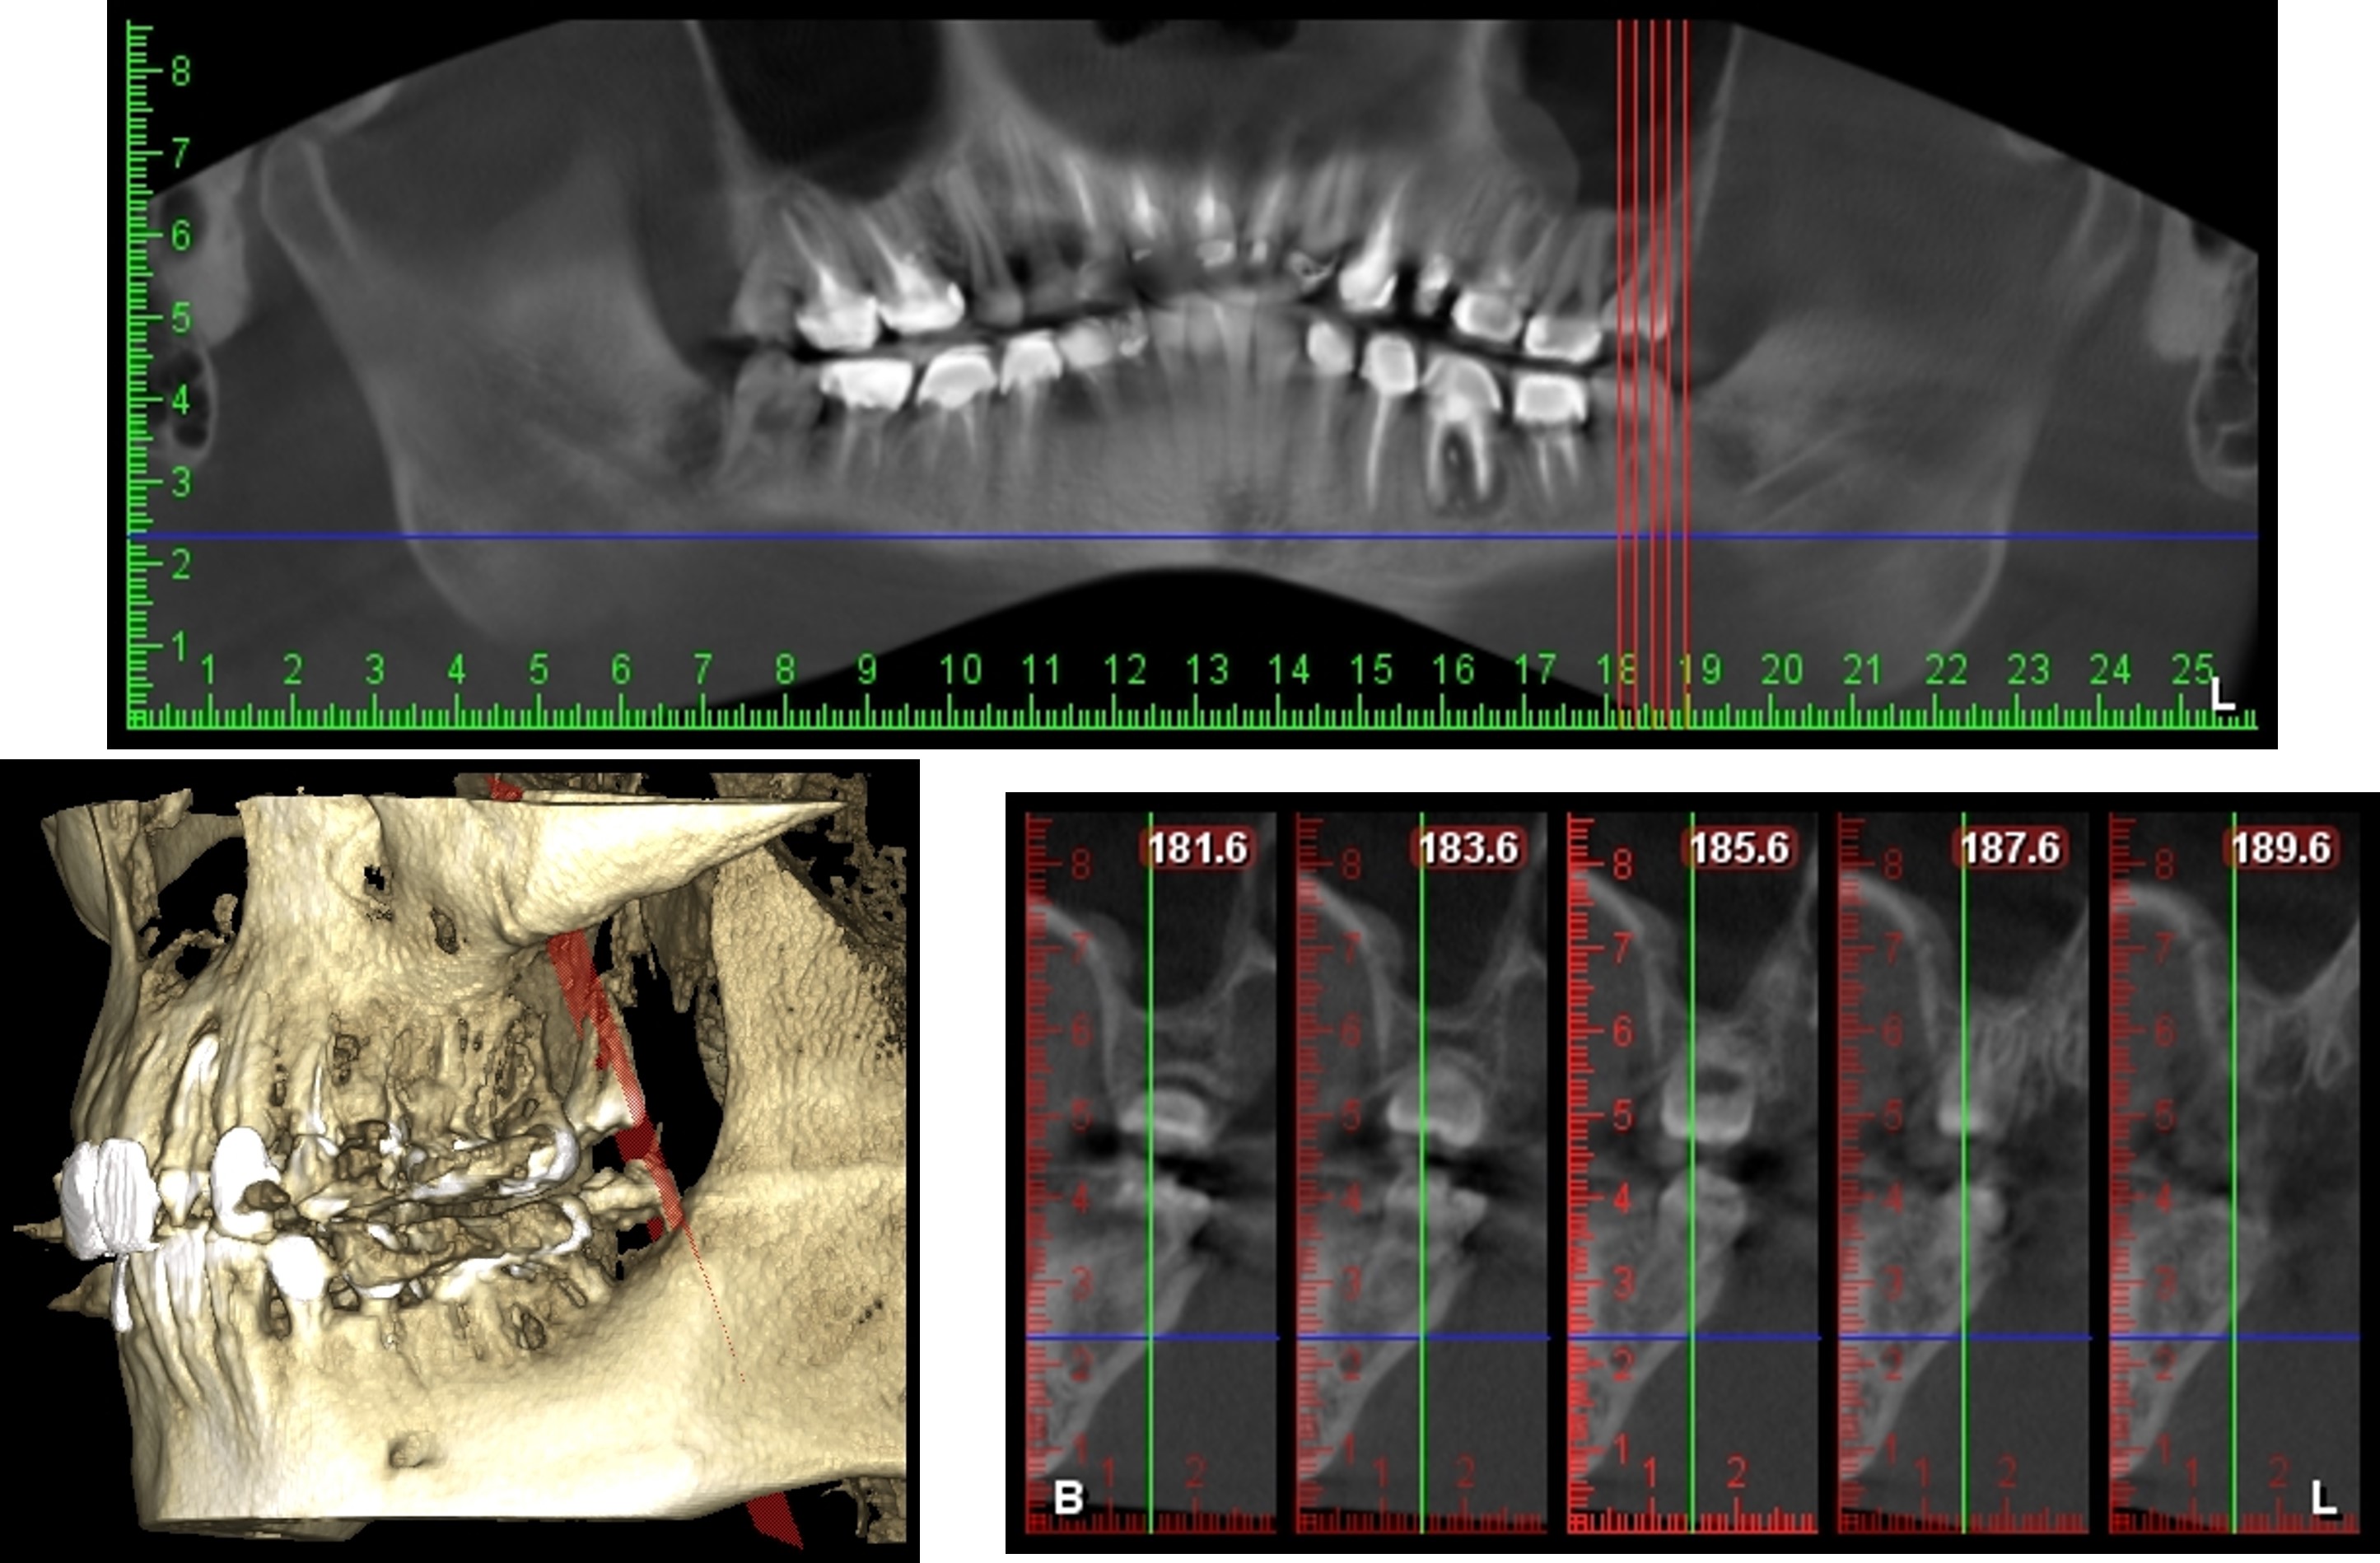

治療前,左下阻生齒深度蛀牙

治療前,環口X光,深度蛀牙

電腦斷層顯示下齒槽神經距離遠